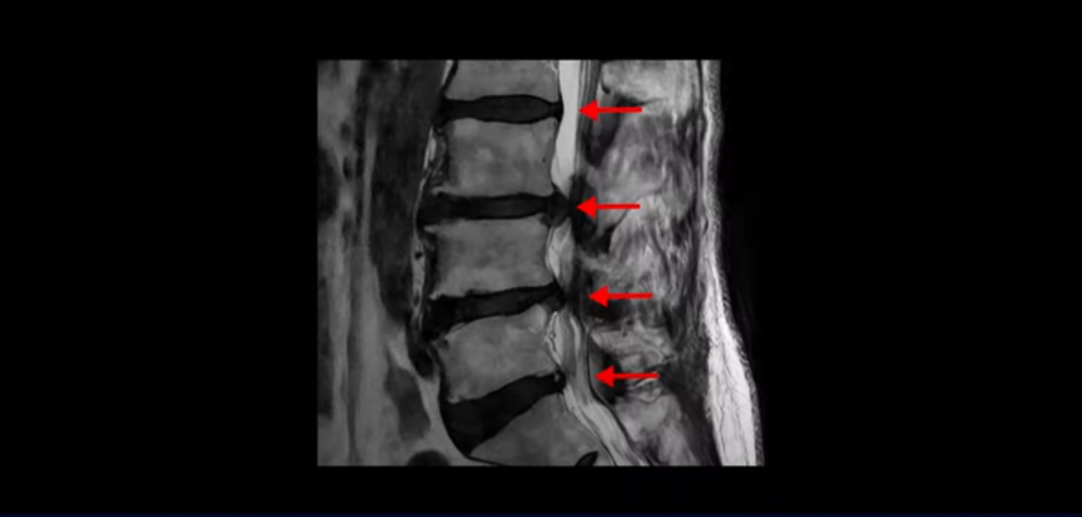

이분은 허리부터 다리, 복숭아뼈까지 극심하게 저리고 아픈 분입니다. MRI를 보시면 허리 4마디가 안 좋습니다.

그중에서도 3번 4번과 4번 5번 마디가 가장 안 좋습니다. 보시다시피 두 마디에 심한 중심성 협착이 있습니다.

이렇게 허리에서 신경이 눌리니까 다리가 저리고 종아리가 터질 듯이 아픕니다. 그래서 걷지를 못하고 가다 쉬고 가다 쉬고 그런 겁니다. 그런데 이런 분들이 수술 없이 치료가 가능한 이유는 근육재활치료와 운동으로 근육이 좋아지면 허리를 더 잘 지탱해 주니까 신경이 덜 눌리게 되는 겁니다. 모든 협착증 환자는 신경 구멍도 좁아져 있지만 근육도 다 망가져 있습니다.

이 환자분처럼 신경이 눌려있는데 어떻게 수술하지 않고 협착증을 치료할 수 있는지 설명 드리겠습니다. 저희가 계속 반복해서 말씀 드리지만, 협착증 증상이 생기고 악화되는 이유는 신경 구멍이 노화로 좁아져서만 그런 게 아닙니다. 나이가 들면서 반드시 근육도 동시에 나빠지기 때문입니다. 신경 구멍이 좁아져 있는 상태에서 근육은 줄어들고 망가지면서 허리를 잘 지지하지 못하니까 신경이 더 눌리는 것입니다. 그러니까 협착증이 주로 60세 나이 든 사람들한테 생기는 것입니다.

그런데도 아직도 많은 분들이 근육의 중요성을 모르고 신경치료만 하고 있습니다. 하지만 근육과 신경은 떼놓고 생각할 수가 없습니다. 근육이 나빠지면 신경 눌림이 심해져서 협착증 증상이 더 악화되고, 또 신경이 많이 눌릴수록 근육도 더 빨리 나빠집니다. 반대로 근육이 좋아지면 신경 눌림이 줄어들고 협착증이 좋아집니다. 신경이 눌린다고 하니까 신경 눌림을 풀어주는 수술만 생각을 하시는 분들이 많은데 근육이 좋아져서 허리를 잘 지지해주면 신경이 덜 눌립니다. 그래서 저희 모커리한방병원은 근육을 좋게 만들기 위해 협착증에 근육재활치료를 하고 있는 겁니다. 근육이 좋아지면 협착증은 반드시 좋아집니다.